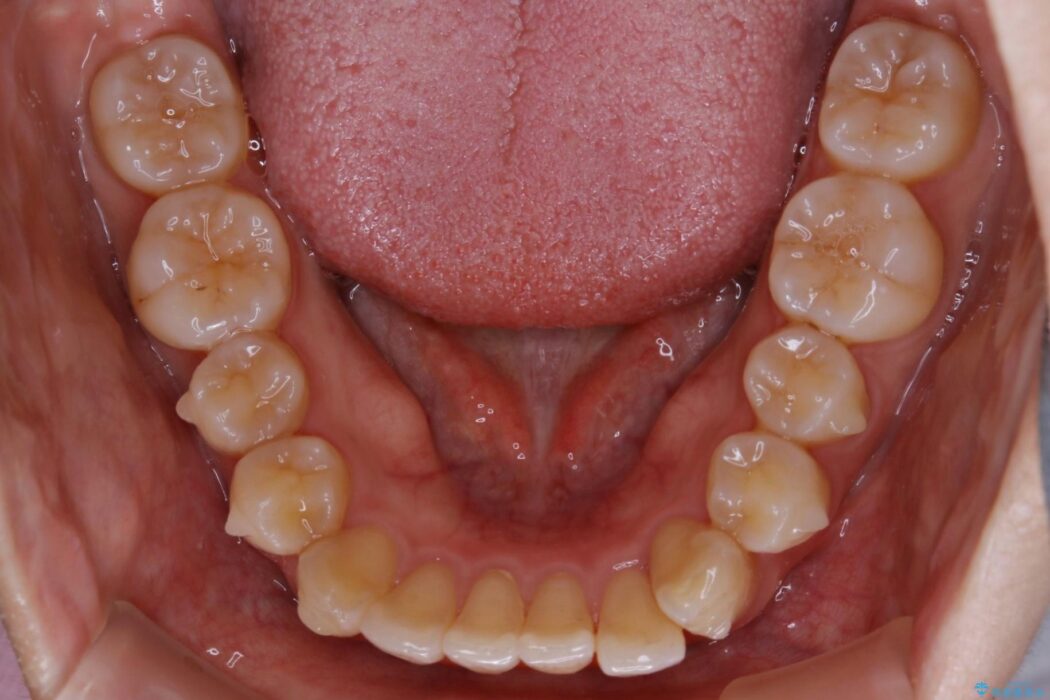

下額前歯が少しガタついていることを気にされて来院されました。

検査をしたところ奥歯の噛み合わせなどに問題が見られなかったため、軽度のねじれがある下顎前歯に焦点を当てた部分矯正の適応が可能と判断し、インビザラインのライトパッケージをご提案しました。

本症例では奥歯に関して問題がほぼ見られなかったため、部分矯正を行うことが可能と判断しました。

通常の全体矯正と比べピンポイントの部分矯正となると、動かす歯が少なくなるため治療期間が格段に短くなり、費用が抑えられることがメリットとして挙げられます。